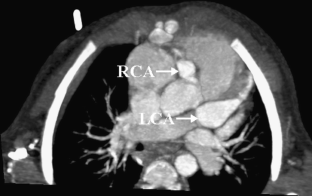

MSCT showed coronary artery injury in 15 of the 48 children. Among these 15 children, 20 coronary artery branches showed complications, including the left coronary artery branches in 15 (31.2%) and the right coronary artery branches in 5 (10.4%). Complications in the left coronary artery branches included dilation in 12 (25.0%) and stenosis, calcification and the combination of the two in one each, and the right coronary artery branches showed dilation; two branches also showed beaded changes. MSCT also showed dilation in the left anterior descending arteries in two children. These children showed no abnormality on 2-D echocardiography.

Fig. 3